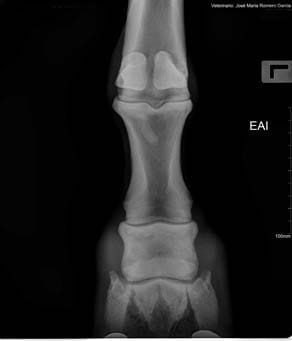

- Diagnóstico y seguimiento de cojeras

- Exámenes pre-compra o compraventa

La radiología digital directa es una herramienta indispensable para el estudio v valoración en numerosas áreas de la atención veterinaria: valoración de cojeras, exámenes pre-compra, estudios radiológicos, diagnósticos más precisos en patologías, heridas, enfermedad…

- Nuevas herramientas de ajuste y valoración. Base de estudios

- Herramientas de medidas más completas y potentes